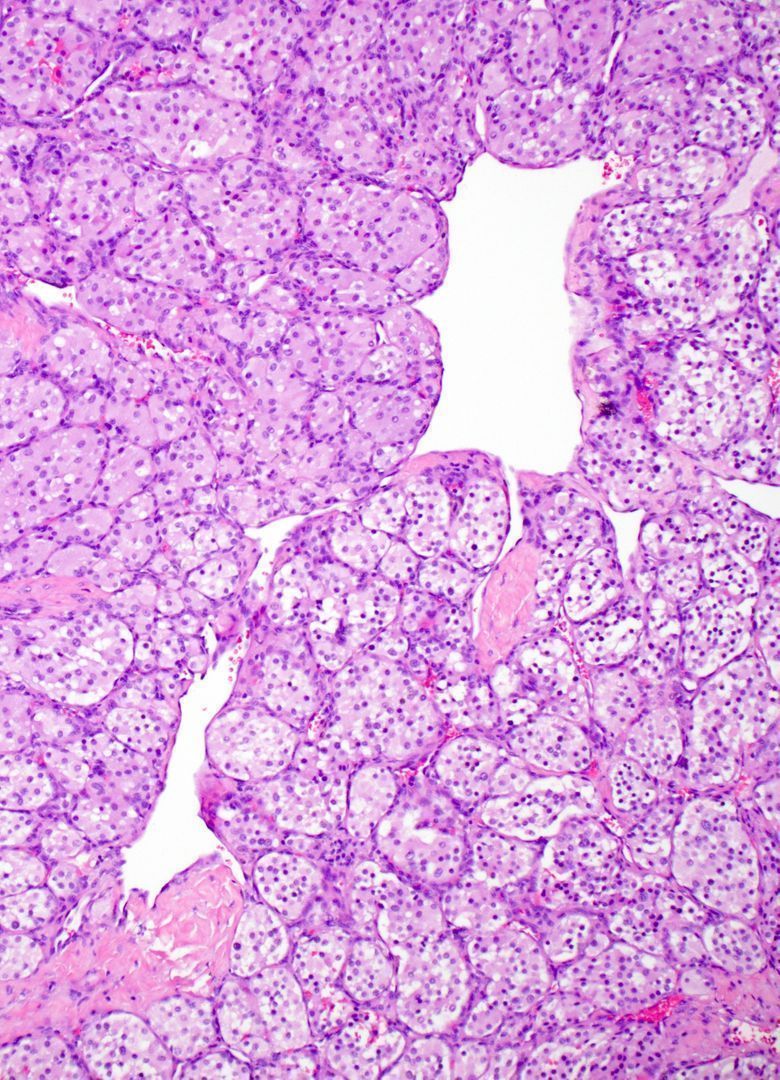

Child with expansile intramedullary bone lesion. What syndromes can this occur in? What gene mutation? Answers & WSI digital slide: kikoxp.com/posts/22455 Video: kikoxp.com/posts/16802 #BSTpath #pathologists #pathTwitter #orthotwitter #radpathmatch #radiology #radstwitter

Child with expansile intramedullary bone lesion.

What syndromes can this occur in? What gene mutation?

Answers & WSI digital slide: kikoxp.com/posts/22455

Video: kikoxp.com/posts/16802

#BSTpath #pathologists #pathTwitter #orthotwitter #radpathmatch #radiology #radstwitter